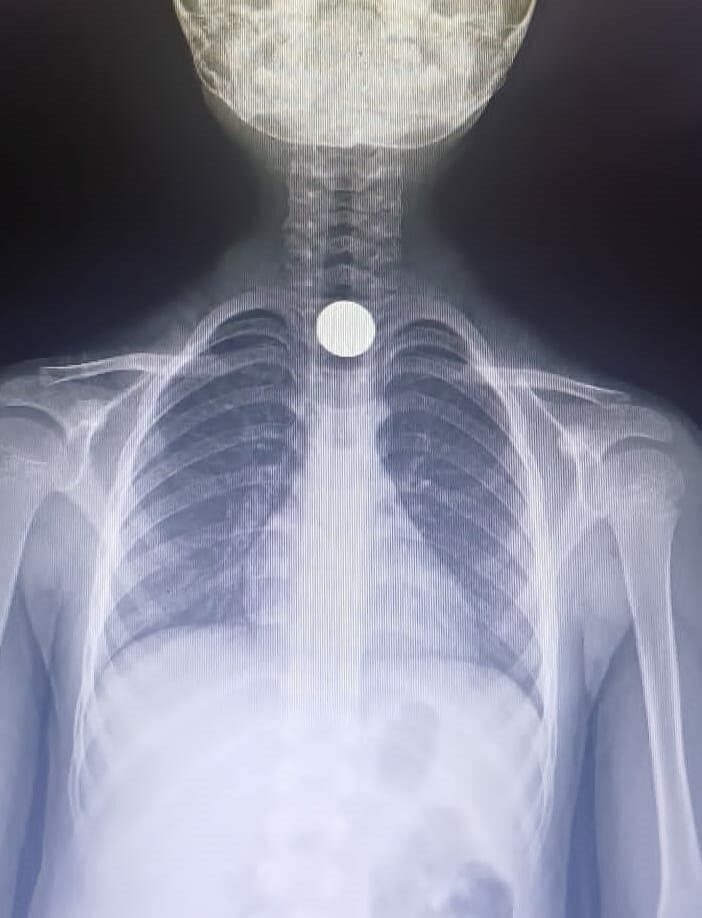

Tetkiklerde, yemek borusuna 50 kuruşluk madeni para kaçtığı tespit edilen Yusuf Z., ambulansla Bursa Yüksek İhtisas Eğitim ve Araştırma Hastanesi’ne sevk edildi.

Yusuf Z.’nin yemek borusundaki para, burada yapılan başarılı ameliyatla çıkartıldı. (DHA)